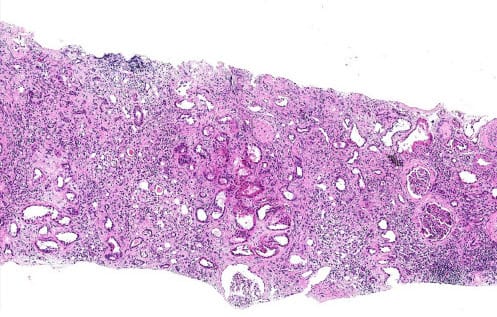

Kidney biopsy with marked interstitial fibrosis and tubular atrophy (IFTA)